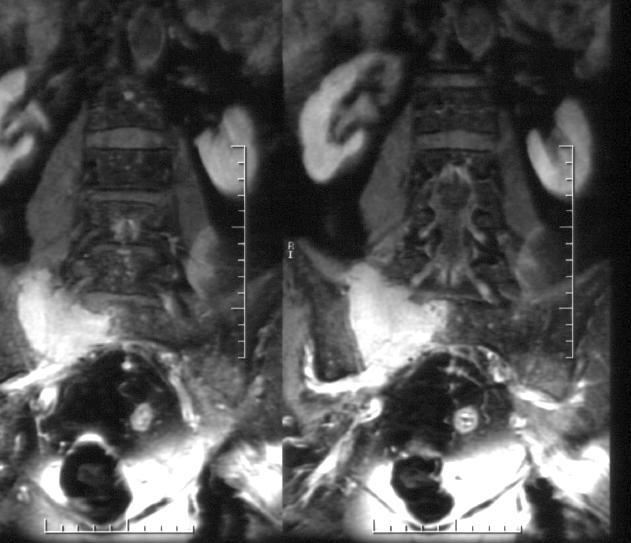

Pe baza acestor investigatii este certificata prezenta unei formatiuni tumorale bine vascularizate la nivel sacrat, cu osteoliza asociata, care se extinde la nivel sacro-iliac drept. Se recomanda completarea investigatiilor cu examinarea RMN cu substanta de contrast a coloanei lombo-sacrate, care confirma descrierea masei osteolitice cu contur neregulat si dimensiuni axiale maxime de 62/63mm la nivelul hemisacrului drept, precum si extensia sacro-iliaca.